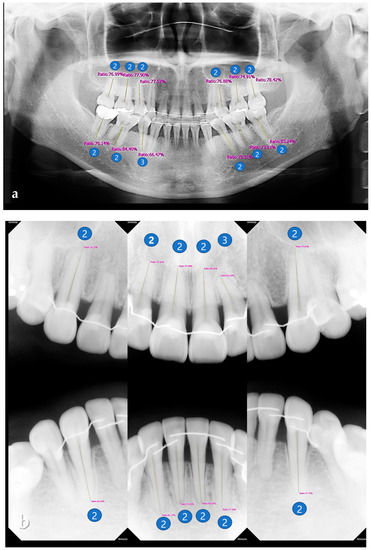

2.3.2. Fluorescent Plaque Index (FPI) Scoring

The FPI score for the fluorescent image of the QLF images was automatically calculated with the “Simple Hygiene Score” function of the proprietary analysis program (Q-ray version 1.24, Inspektor Research Systems BV) (Figure 3). FPI was a score calculated by applying two variables (A30 and A120), which are regions of red fluorescent plaques corresponding to pixels with ΔR > 30% and ΔR > 120%, to a specific function. FPI scores were calculated in one of six categories (from 0 to 5) (Figure 4), according to the classification rules as follows [24]. (1) A30 < 0.5 % and A120 < 0.4%, FPI score was classified as 0; (2) 0.5% ≤ A30 < 2.5% and A120 < 0.4% was classified as FPI score 1; (3) 2.5%≤ A30 < 4.5% and A120 < 0.4% was classified as FPI score 2; (4) 4.5 % ≤ A30 or 0.4% ≤ A120 < 0.9% was classified as FPI score 3; (5) 0.9% ≤ A120 < 2.1% was classified as FPI score 4; (5) 2.1% ≤ A120 was classified as FPI score 5. The variable ΔR indicates that porphyrin, a metabolite secreted by bacteria, is present in the oral cavity and assesses the level of bacterial activity.

Figure 4.

FPI is a score calculated by applying two variables (A30 and A120), which are regions of red fluorescent plaques corresponding to pixels with ΔR > 30% and ΔR > 120%, to a specific function. FPI scores were calculated in one of six categories (from 0 to 5).